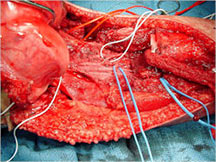

Surgery:

- Wide surgical resection/limb salvage

Limb Sparing Surgery

- Surgical principles are the same as those employed for conventional osteosarcoma

- Nowadays, most patients can be treated with a limb sparing resection instead of an amputation

- Prosthetic replacements, cadaver allografts, vascularized bone grafts as well as other methods have been used to reconstruct extremities after tumors are removed